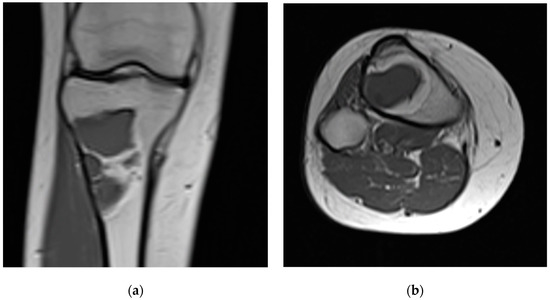

3 | 17 F | 1 | Right proximal tibia | 58 | Fibrous dysplasia | 22 |

9 | 27 F | 1 | Left tibial diaphysis | 41 | Fibrous dysplasia | 23 |